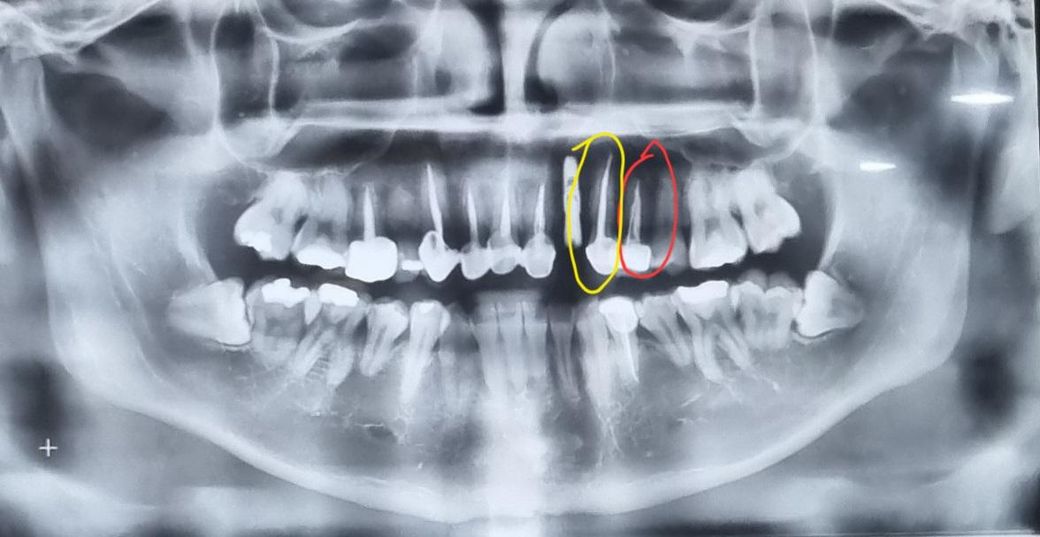

이 치아는 왜 이렇게 얇은걸까요????

저 빨간색 동그라미는 그냥 크리운을 한건가요?

포스트 크라운을 한건가요?

포스트 크라운을 한거라면 왜 옆에 노란색은 하얀색으로 굵은데 빨간색은 없어? 연해 보이나요??

빨간색 치아 부위는 신경치료 후 크라운 한 것입니다. 작은어금니로 신경관 자체가 굵어서 x-ray 상에서 넓어 보이는 것입니다.

동그라미 친 치아는 신경치료를 하고나서 크라운 치료를 하신거 같습니다. 포스트를 하기위해서 신경치료를 한 gp콘을 제거하고 그 안에 포스트를 넣어서 그렇게 보이는거 같습니다.

연하다 굵다는 것이 명확히 이해되지는 않지만 신경이 두개이기 때문에 엑스레이에는 다르게 나옵니다.

빨간색 동그라미 쳐진 치아는 신경치료까지 하고 신경관을 치과용 재료로 채운 뒤 크라운으로 씌운 것으로 보입니다. 포스트는 안되어 있는 것 같습니다.